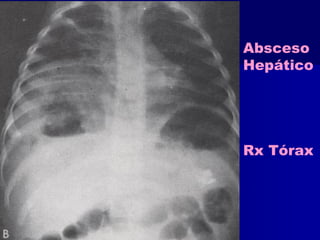

Absceso

Hepático

Rx Tórax

 RRxx TTóórraaxx yy AAbbddoommeenn